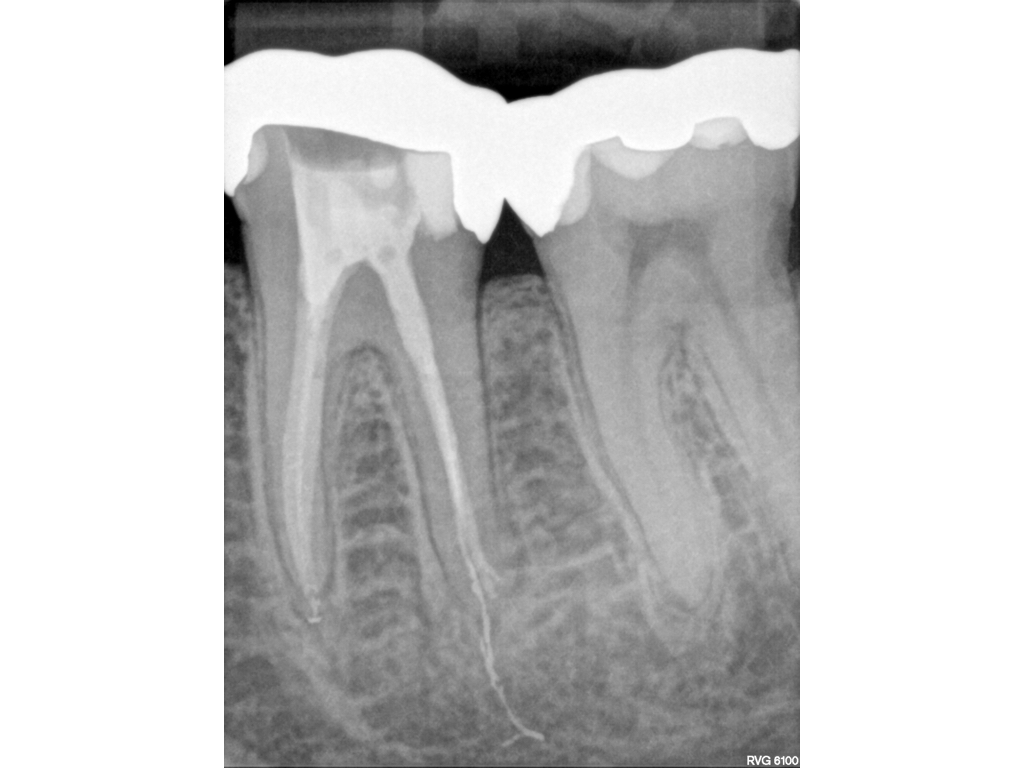

Metalift (2).006 Veröffentlicht 2. Dezember 2019 am 1024 × 768 in Metalift (2) WF Kontrolle und Einprobe der Restauration